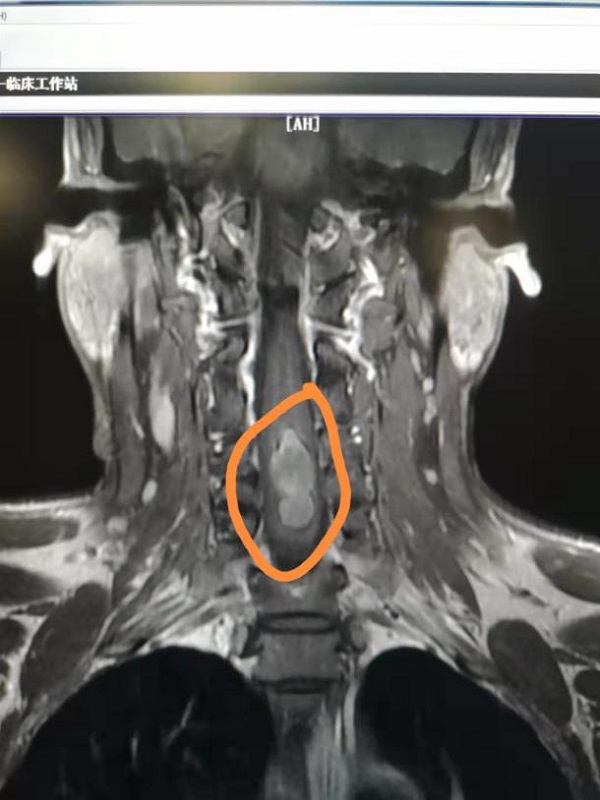

术前磁共振显示:患者颈4-6水平髓内大小为3.4cmx0.9cm异常强化灶